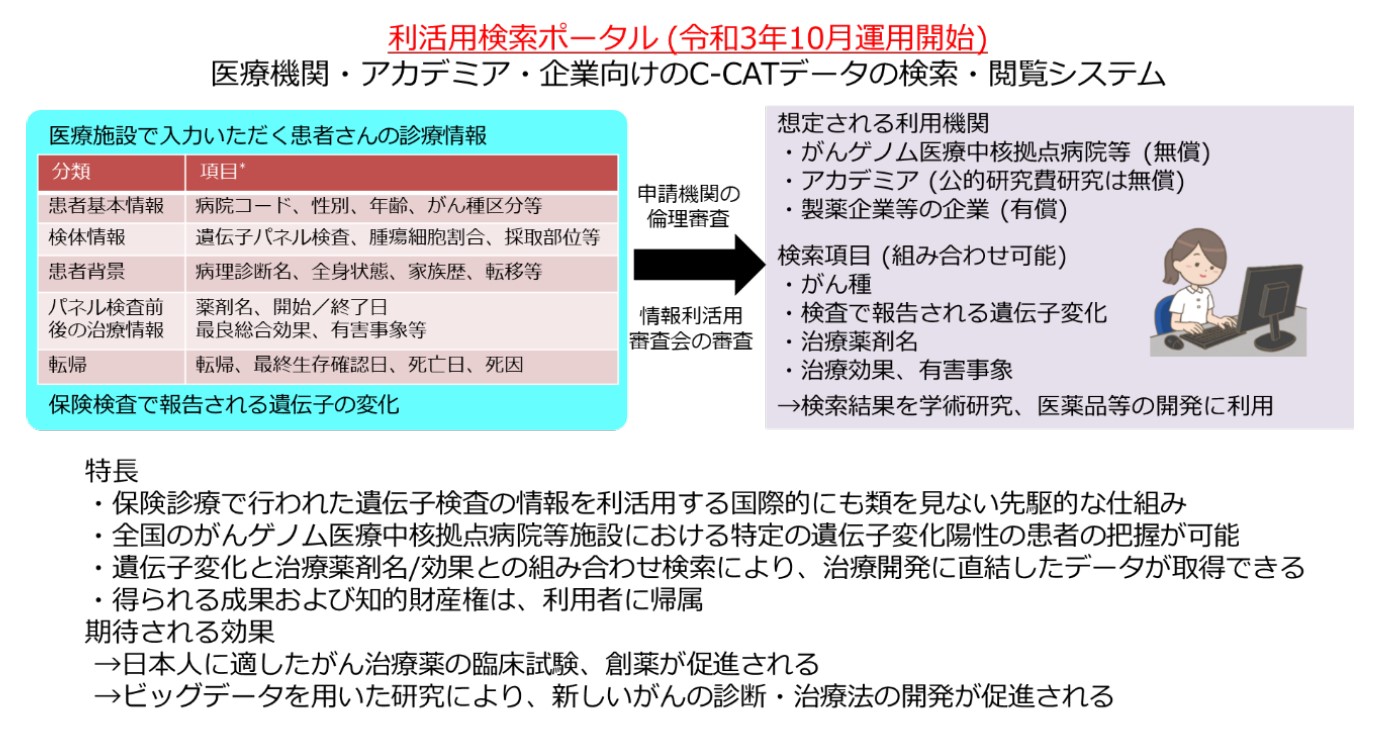

がん遺伝子パネル検査データの研究開発利活用が開始

がんゲノム情報管理センター(C-CAT)が、がんゲノム医療で行われたがん遺伝子パネル検査の情報を研究・開発に利活用いただ...